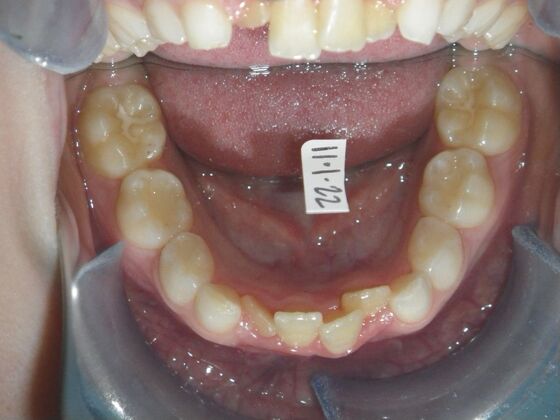

This sweet patient presented with constricted upper and lower arches and blocked out, rotated upper and lower anterior teeth. The upper centrals were leaning backward and had the lower arch captured preventing anterior advancement. Treatment was begun on the upper arch first, followed with placement of lower lip bumper to allow for lateral and anterior development of lower arch. Eventually placed lower brackets with strategic slenderizing of primary teeth to allow permanent incisor to assume their proper placement. All accomplished within 12 months and straight-wire appliances.